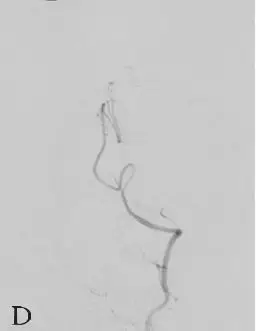

DSA:急诊全脑血管造影提示右侧颈内动脉发出变异的原始三叉动脉,该三叉动脉直接向右侧小脑前下动脉(AICA)供血区域供血,在原始三叉动脉自颈内动脉发出部位可见1枚梭形动脉瘤(图18-1B、C),右侧椎动脉发育较差,仅供血小脑后下动脉(PICA)区域(图18-1D)。右侧小脑前下动脉(AICA)未见显影,可见基底动脉发出的部分回旋支显影(图18-1E)。其余血管造影未见明显异常。

D:右侧椎动脉造影;